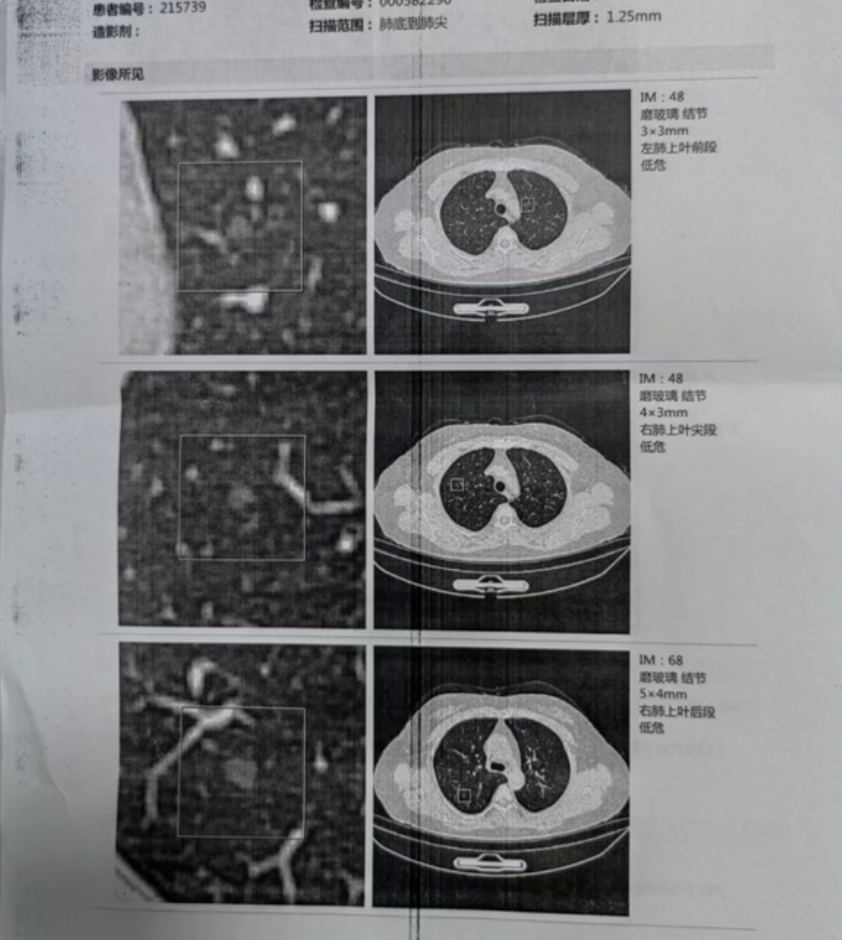

相较于传统CT影像依据结节典型特征进行病灶侵袭性的判断,人工智能依托机器深度学习方法和计算机软件技术,可准确提取肺结节中具有重要诊断参考价值的图像微特征,并结合人工智能算法,有望针对肺结节开展分级诊断及其更深层面的病理亚型预判,指导临床决策和制定最优手术规划。目前人工智能技术已被证实可以较好地用于以GGN(毛玻璃状结节)表现为主的肺腺癌病灶的浸润性判断,可以为早期肺癌的个体化诊治提供重要的参考依据。

现阶段,肺结节人群较庞大,但并非所有的肺结节发现以后都需要立即接受治疗,绝大多数都是建议选择随访观察为主;具体随诊方案往往需根据肺结节基线检查特征进行拟定,通常推荐采用高分辨率CT行<1 mm的薄层扫描,同时建议进行肺结节多角度影像重建。目前,相关指南建议将肺结节分类分层管理,随诊方式应按结节分类及恶性风险分层进行区分。

针对肺结节的多次随访,相关研究提示,在多次随访数据监测中,人工智能技术在协助评估肺结节体积及其形态变化方面具备一定优势,尤其是在结节倍增时间变化和形态学改变等重要观察数据上,可以为肺结节随访提供参考依据,协助制定科学合理的个体化随访间期。